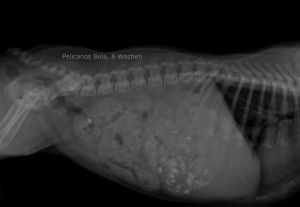

PELICANOS BELA

| Name | PELICANOS BELA |

| Sex | Male |

| Birthday | 28.03.2017 |

| Color | Brindle |